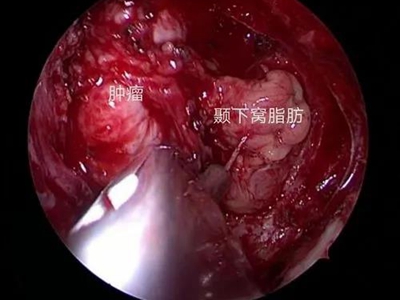

鼻咽纤维血管瘤又名“男性青春期出血性鼻咽血管纤维瘤”,是起源于鼻咽部的良性肿瘤,好发于14-25岁的男性青年,在鼻咽部的良性肿瘤中居首位。侵犯周围组织的能力较强,随瘤体的不断增大,易扩展到眼眶、鼻腔,甚至颅内,导致严重的并发症。

3、其他症状:肿瘤压迫咽鼓管,引起耳鸣、耳闭及听力下降。肿瘤侵入邻近结构则出现相应症状,如侵入眼眶,则出现眼球突出,视力下降;侵入翼腭窝引起面颊部隆起;侵入颅内压迫神经引起头痛及其他颅神经瘫痪。

鼻咽纤维血管瘤以手术切除为主要治疗方式。围手术期需要进行血管栓塞,术中控制低血压等。少数不能立即手术的患者,可酌用放射治疗、注射硬化剂、内服激素等治疗,等待手术时机。